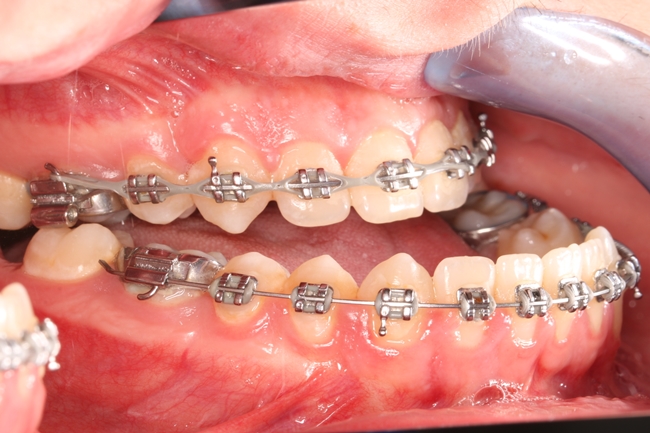

Wady szkieletowe należą do grupy zaburzeń rozwojowych o charakterze zarówno dziedzicznym, jak i nabytym. Ujawniają się najczęściej w okresie dojrzewania, kiedy następuje intensywny skok wzrostowy. Czasami jednak już od najmłodszych lat życia rodzice obserwują, że dziecko ma problemy na przykład z odgryzaniem pokarmu, ponieważ zęby górne i dolne są ustawione w nieprawidłowych relacjach wobec siebie. Jedna z częściej występujących wad gnatycznych, w polskiej nomenklaturze określana jako progenia, manifestuje się tym, że zęby żuchwy są ustawione doprzednio w stosunku do zębów szczęki (ryc. 1, 2). Wada ta może być wyleczona tylko operacyjnie (ryc. 3, 4). Zaburzenia szkieletowe mogą być związane zarówno z nadmiernym rozwojem, jak i niedoborem rozwoju odpowiednich kości. W takich wypadkach najczęściej manifestują się nieprawidłowym zgryzem lub brakiem kontaktu pomiędzy zębami szczęki i żuchwy, co utrudnia funkcjonowanie i skłania pacjentów do poszukiwania pomocy.

Ryc. 3. Zgryz przed leczeniem chirurgicznym.